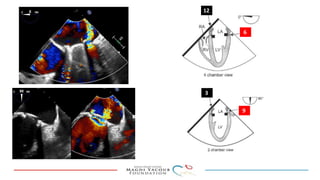

This document provides an overview of percutaneous prosthetic valve leakage (PVL) closure, including indications, approaches, techniques, and closure devices. It discusses that over 210,000 prosthetic valve surgeries are performed each year, with PVL occurring in some cases. While surgical closure has a high mortality rate, percutaneous closure has a procedural success rate of 86% and less complications. Indications for closure include symptomatic heart failure, hemolysis, rocking prosthesis, or leaks over 30% of the sewing ring. Techniques discussed include retrograde and transapical approaches using devices like the Amplatzer and Occlutech plugs. A team approach and techniques like sequential deployment are emphasized for